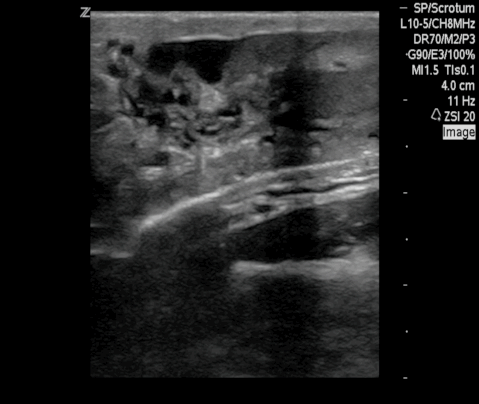

Dance Of Live Adult Filarial Worms Is A Reliable Sign Of Scrotal Filarial Infection Chaubal 2003 Journal Of Ultrasound In Medicine Wiley Online Library

Figure 2 From The Filarial Dance Sign In Scrotal Filarial Infection Semantic Scholar

Composite Of Scrotal Ultrasound Findings In Different Men Before Download Scientific Diagram

Scrotal Filariasis The Importance Of Filarial Dance Sign In Scrotal Ultrasound

Scrotal Ultrasound Shows The Characteristic Filarial Grepmed